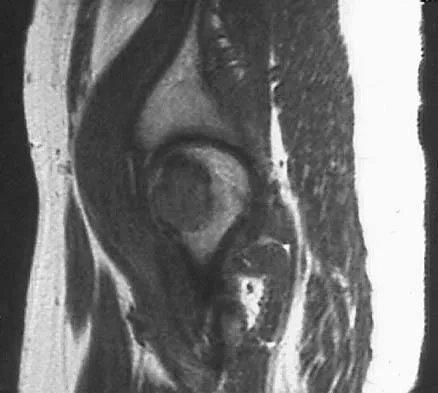

Figure 42 shows the sagittal T2-weighted MRI scan of a patient's right knee. These findings are most commonly seen with a complete tear of the

The MRI scan reveals disruption of the lateral capsule and ligaments with fluid in the soft tissues laterally. Additionally, there is a large bone bruise on the medial femoral condyle. This combination indicates injury to the posterolateral complex. These injuries often have coexisting anterior and/or posterior cruciate ligament injuries. Failure to recognize the posterolateral corner injury can lead to failure of anterior or posterior cruciate ligament reconstructions. LaPrade RF, Gilbert TJ, Bollom TS, et al: The magnetic resonance imaging appearance of individual structures of the posterolateral knee: A prospective study of normal knees and knees with surgically verified grade III injuries. Am J Sports Med 2000;28:191-199.